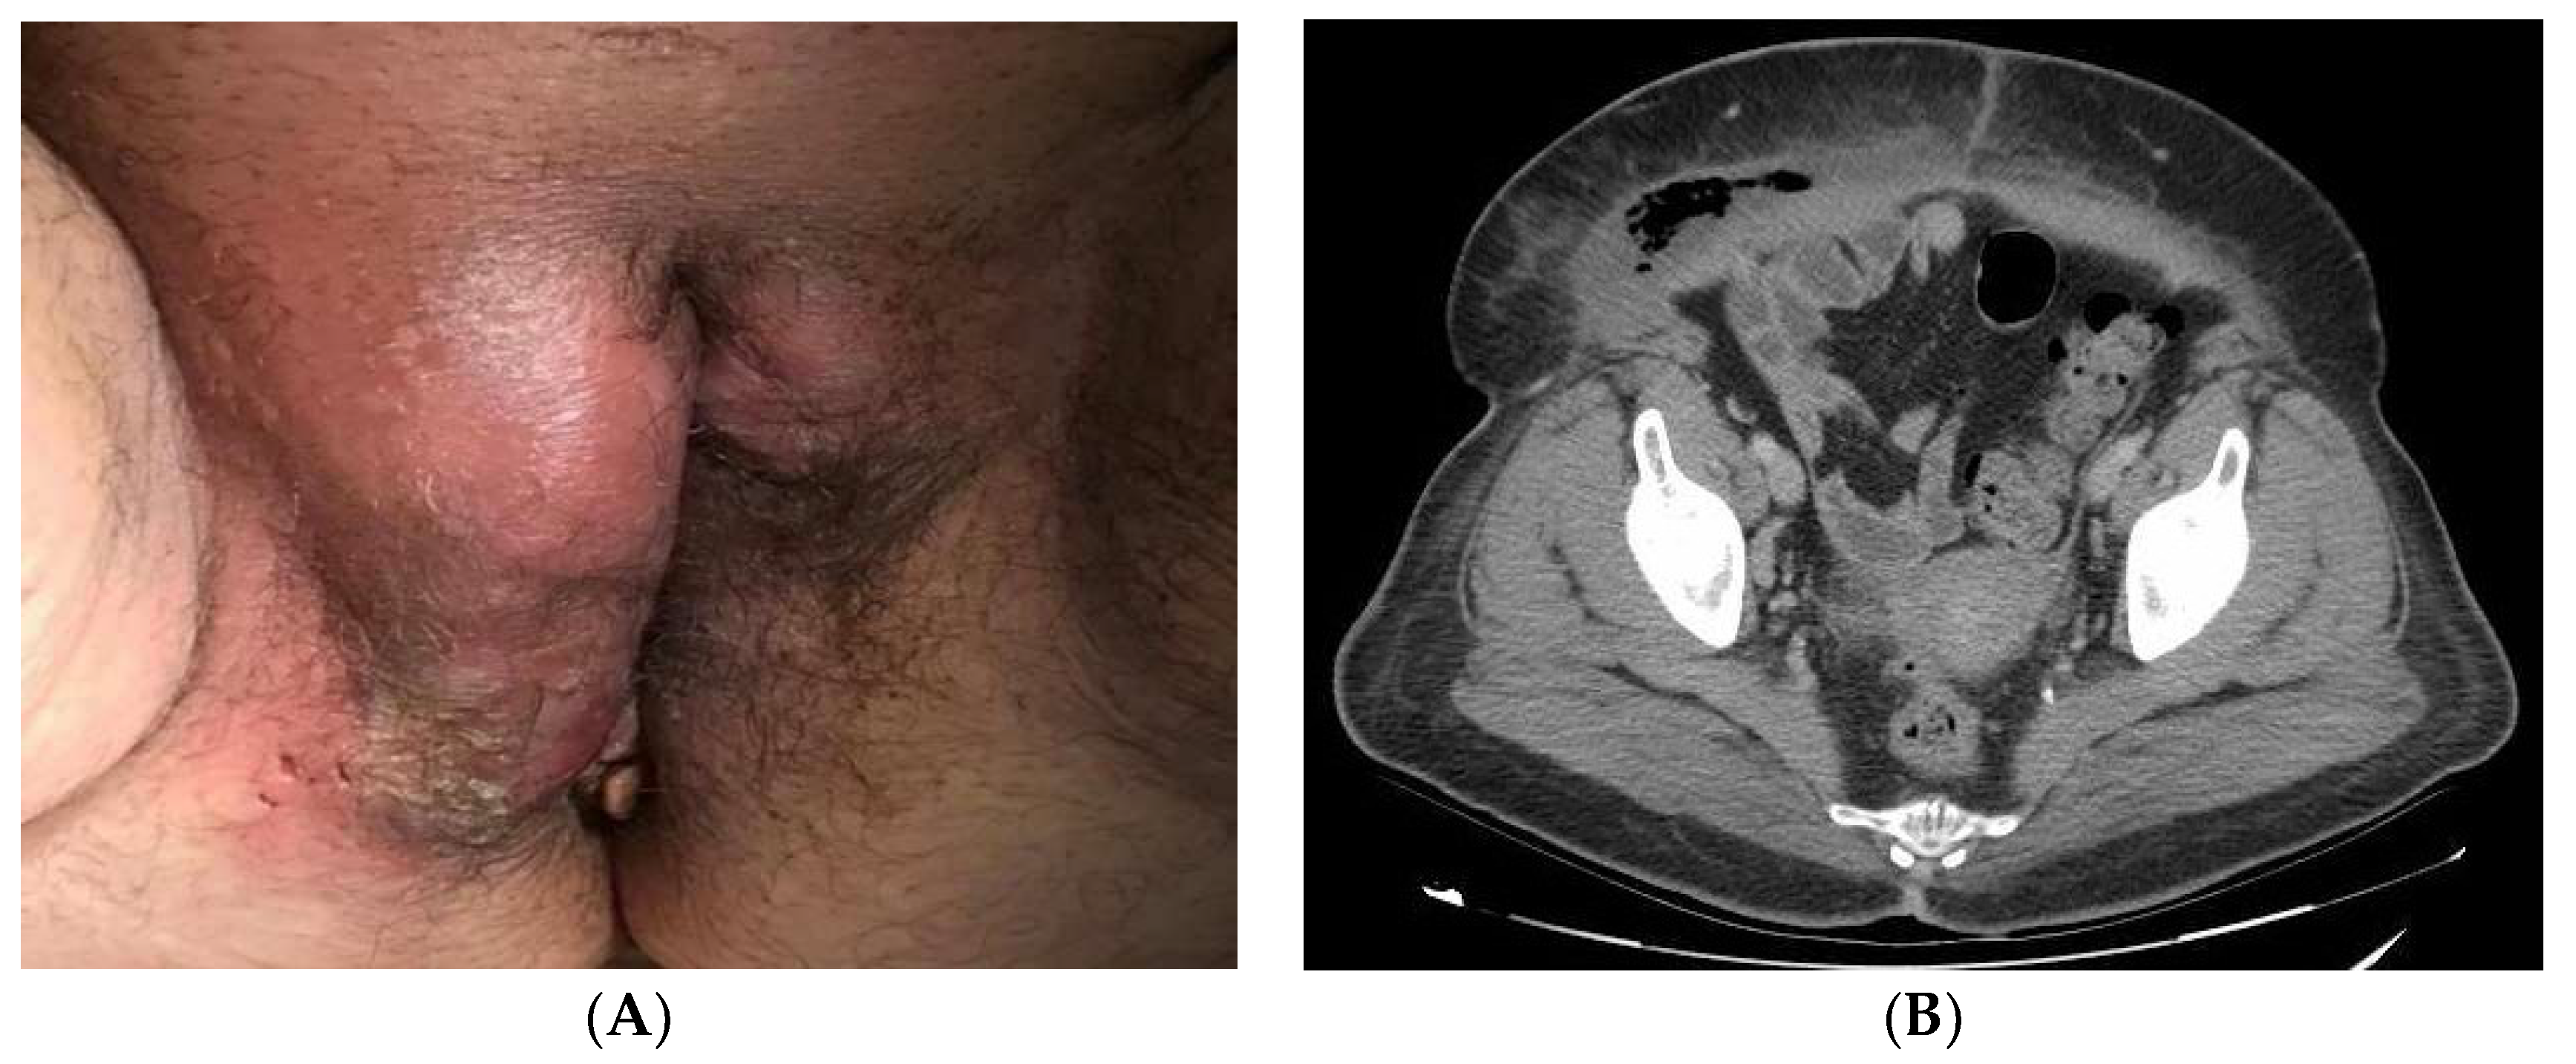

According to the initial evaluation, the patient was febrile (39 °C), tachycardic (123 beats/min), with blood pressure of 146/78 mmHg and respiratory rate of 22 breaths/min. The examination revealed a huge phlegmonous abscess on the right labia majora that extended to the mons pubis (Figure 1A). Rest of the examination was unremarkable. Laboratory workup revealed blood glucose of 243 mg/dL, mild leukocytosis (16,450/L) with 80% neutrophils and C-reactive protein (RCP) of 492 mg/dL. Normal coagulation times. No more unaltered parameters. A CT of the abdomen and pelvis revealed important inflammatory changes and air inside the soft tissues of the genital area extending to the right iliac and paraumbilical fossa compatible with FG (Figure 1B).

Figure 1.

(A): Perineal abscess with induration of surrounding tissue. The most common onset site of FG is the labia majora. (B): CT of the abdomen and pelvis showing areas with gas revealing necrotic tissue from gangrene.